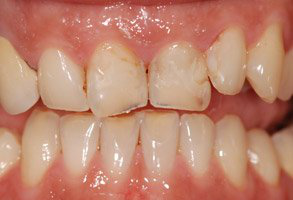

Les 4 incisives maxillaires sont légèrement usées et portent des résines disgracieuses et changées régulièrement. La patiente souhaite un sourire agréable et plaisant en permanence.

Les 4 facettes sont posées en fin d’après-midi.